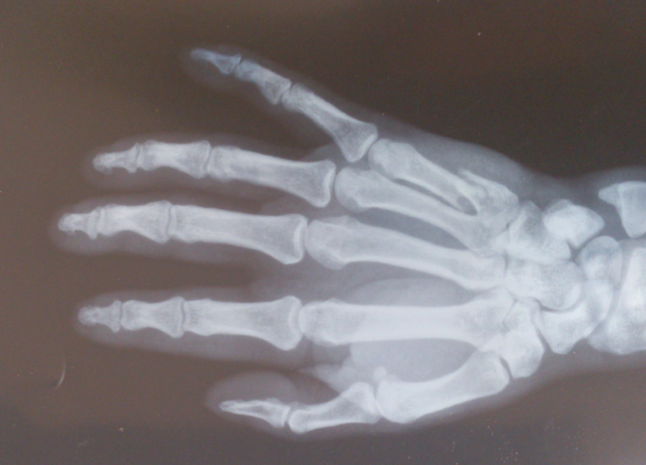

本型骨折的X線特點是第一掌骨近端基底部凹形關(guān)節(jié)面的一半骨折,一半脫位。骨折線從凹形關(guān)節(jié)面的中心斜行向掌側(cè)約1cm處,骨折塊留在掌、尺側(cè)多無移位,而第一掌骨基底部的其余部分受外展拇長肌的牽拉和拇屈肌的收縮向背、外側(cè)半脫位,第一掌骨向掌側(cè)屈曲。

第一掌骨基部骨折